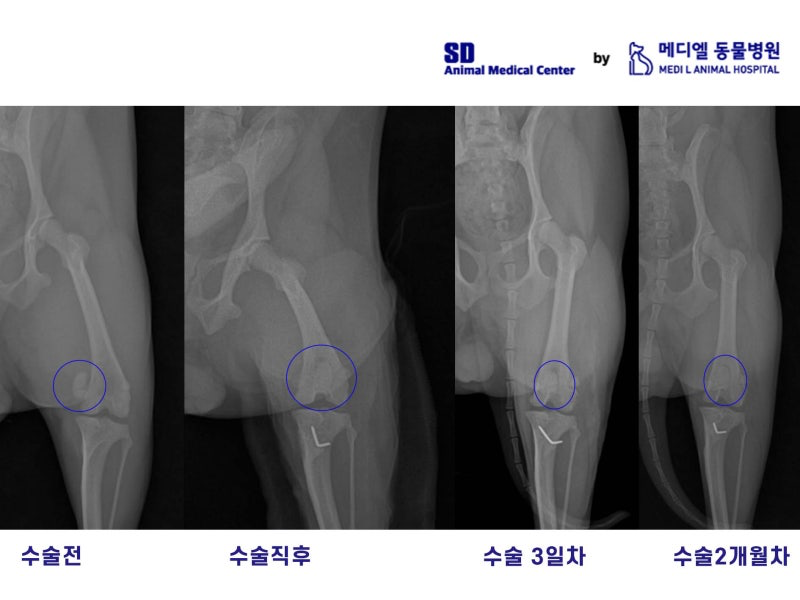

환자의 후지 방사선 비교 사진

이 환자의 수술 전, 수술직후, 수술3일차, 수술2개월차의 비교사진입니다.

수술전에는 눈에 띄게 내측으로 빠져있던 슬개골이 수술직후에 자리를 잡은게 보이고, 3일차에도 무리없이 유지되고있습니다.

2개월차에 찍은 방사선 사진에서도 자리를 잘 잡은 모습이고, 보호자님께서도 아이가 다리를 아파하지 않고 잘 뛰어다녀서 만족하셨습니다.